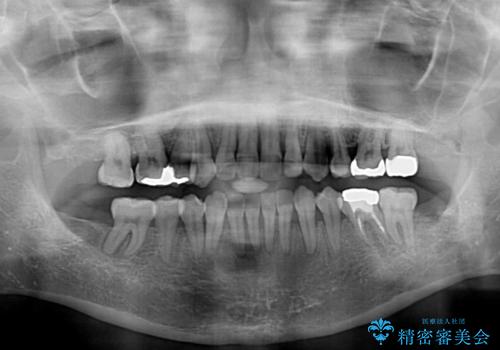

- 奥歯のむし歯を気にして来院された患者様です。

当初は右下の虫歯治療のみを希望されていましたが、虫歯治療に際して部分矯正が必要であったため、治療方法について説明をすると、全体的に歯列不正が気になっているとのことで、全顎矯正を検討することとなりました。

口元の突出感とデコボコがあり、上下左右の小臼歯4本を抜歯して矯正治療を行う方針としました。(右上は欠損のため計3本抜歯)

むし歯となっている歯は状態が悪く、将来的に抜歯となる可能性が高かったため、定石で抜歯させる小臼歯の代わりにむし歯となっている大臼歯を抜歯し、ワイヤー装置にて矯正治療を行うこととしました。